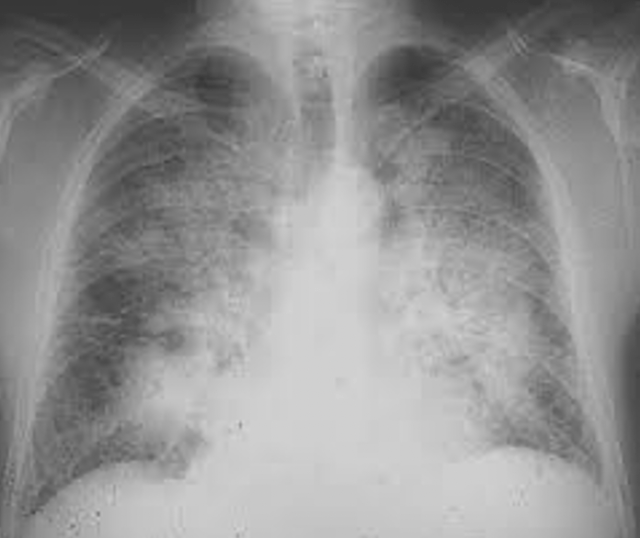

In ARDS, the underlying pathology of COVID-19, the affected body organ is the lung, and that’s what it looks like in imaging:

The pulmonary alveoli (sacs) are filled with air, which appears in black in the image.

Abnormal lung CT scan (ARDS)

WARNING, these images are not specific to a COVID-19! We find them in diffuse infiltrative pneumopathies (PID), including acute hypoxemic interstitial pneumopathies that can be found in intra-alveolar hemorrhages, drug-induced pneumopathies (amiodarone), toxic pneumopathies and system diseases as well as vasculitis. They are found in a group of pulmonary pathologies grouped under the generic term ARDS.

ARDS can be caused by a large number of causes, intra- or extra-pulmonary, infectious or non-infectious.

So, as we can see, the frosted glass lesions described as typical of a COVID-19, are typical of ARDS, not of any particular cause.

They are found in particular in infectious pneumonia with so-called atypical germs, such as Mycoplasma Pneumoniae, Chlamydia Pneumoniae or Legionella Pneumophila, but also in non-infectious pneumopathies (PID or diffuse infiltrative pneumopathies). A differential diagnosis must always be made, especially in people with one or more severe comorbidities (diabetes, obesity, chronic renal, pulmonary or cardiac disease, etc.), which is the case for most people admitted to intensive care units during the COVID period.